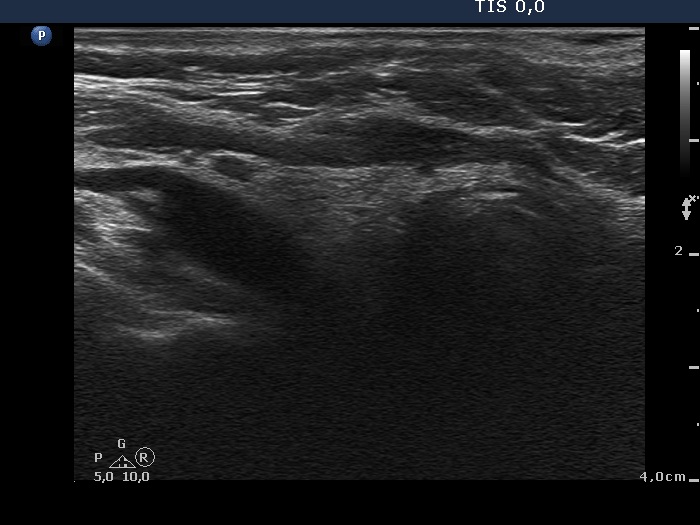

The role of complex diagnosis - oxyphilic lesions - Case 6.

4 years after initial investigation (ultrasonographic picture 2)

Right lobe, longitudinal scan.